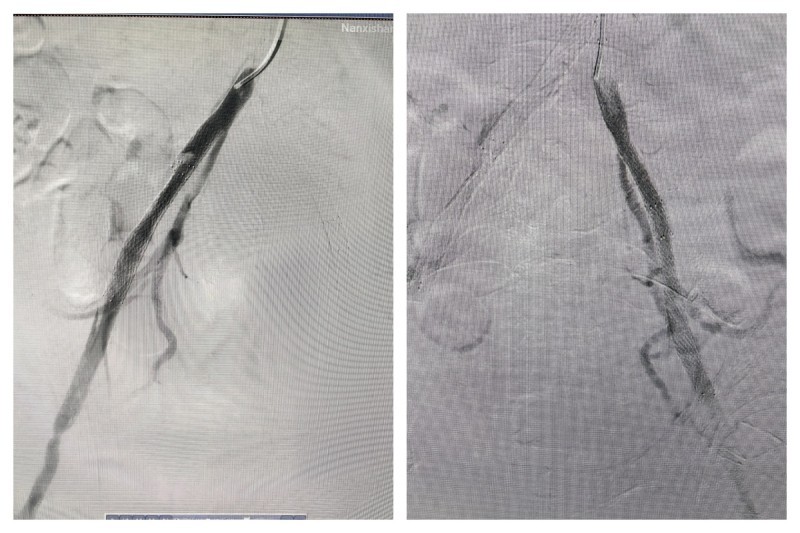

然而,面对如此严峻的挑战,南溪山医院心脏大血管外科的医疗团队并没有退缩。他们迅速为胡某安排了紧急手术。手术中发现,胡某的病情比发病时更为严重。术中造影显示,其主动脉夹层真腔十分细小,左侧髂总动脉闭塞,右侧髂动脉以假腔供血为主。这一情况给手术带来了巨大的困难。

然而,医生们并未退缩,他们凭借着丰富的经验和精湛的技术,另辟蹊径,从上往下成功找到真腔,并顺利完成了手术。在胸主动脉近端置入覆膜支架一枚,覆盖内膜破口;开通闭塞的左髂总动脉并置入支架;右髂动脉细小真腔内也成功置入支架。手术成功封堵住主动脉内膜破口并恢复下肢供血,挽救了胡某的生命并保住了他的下肢。